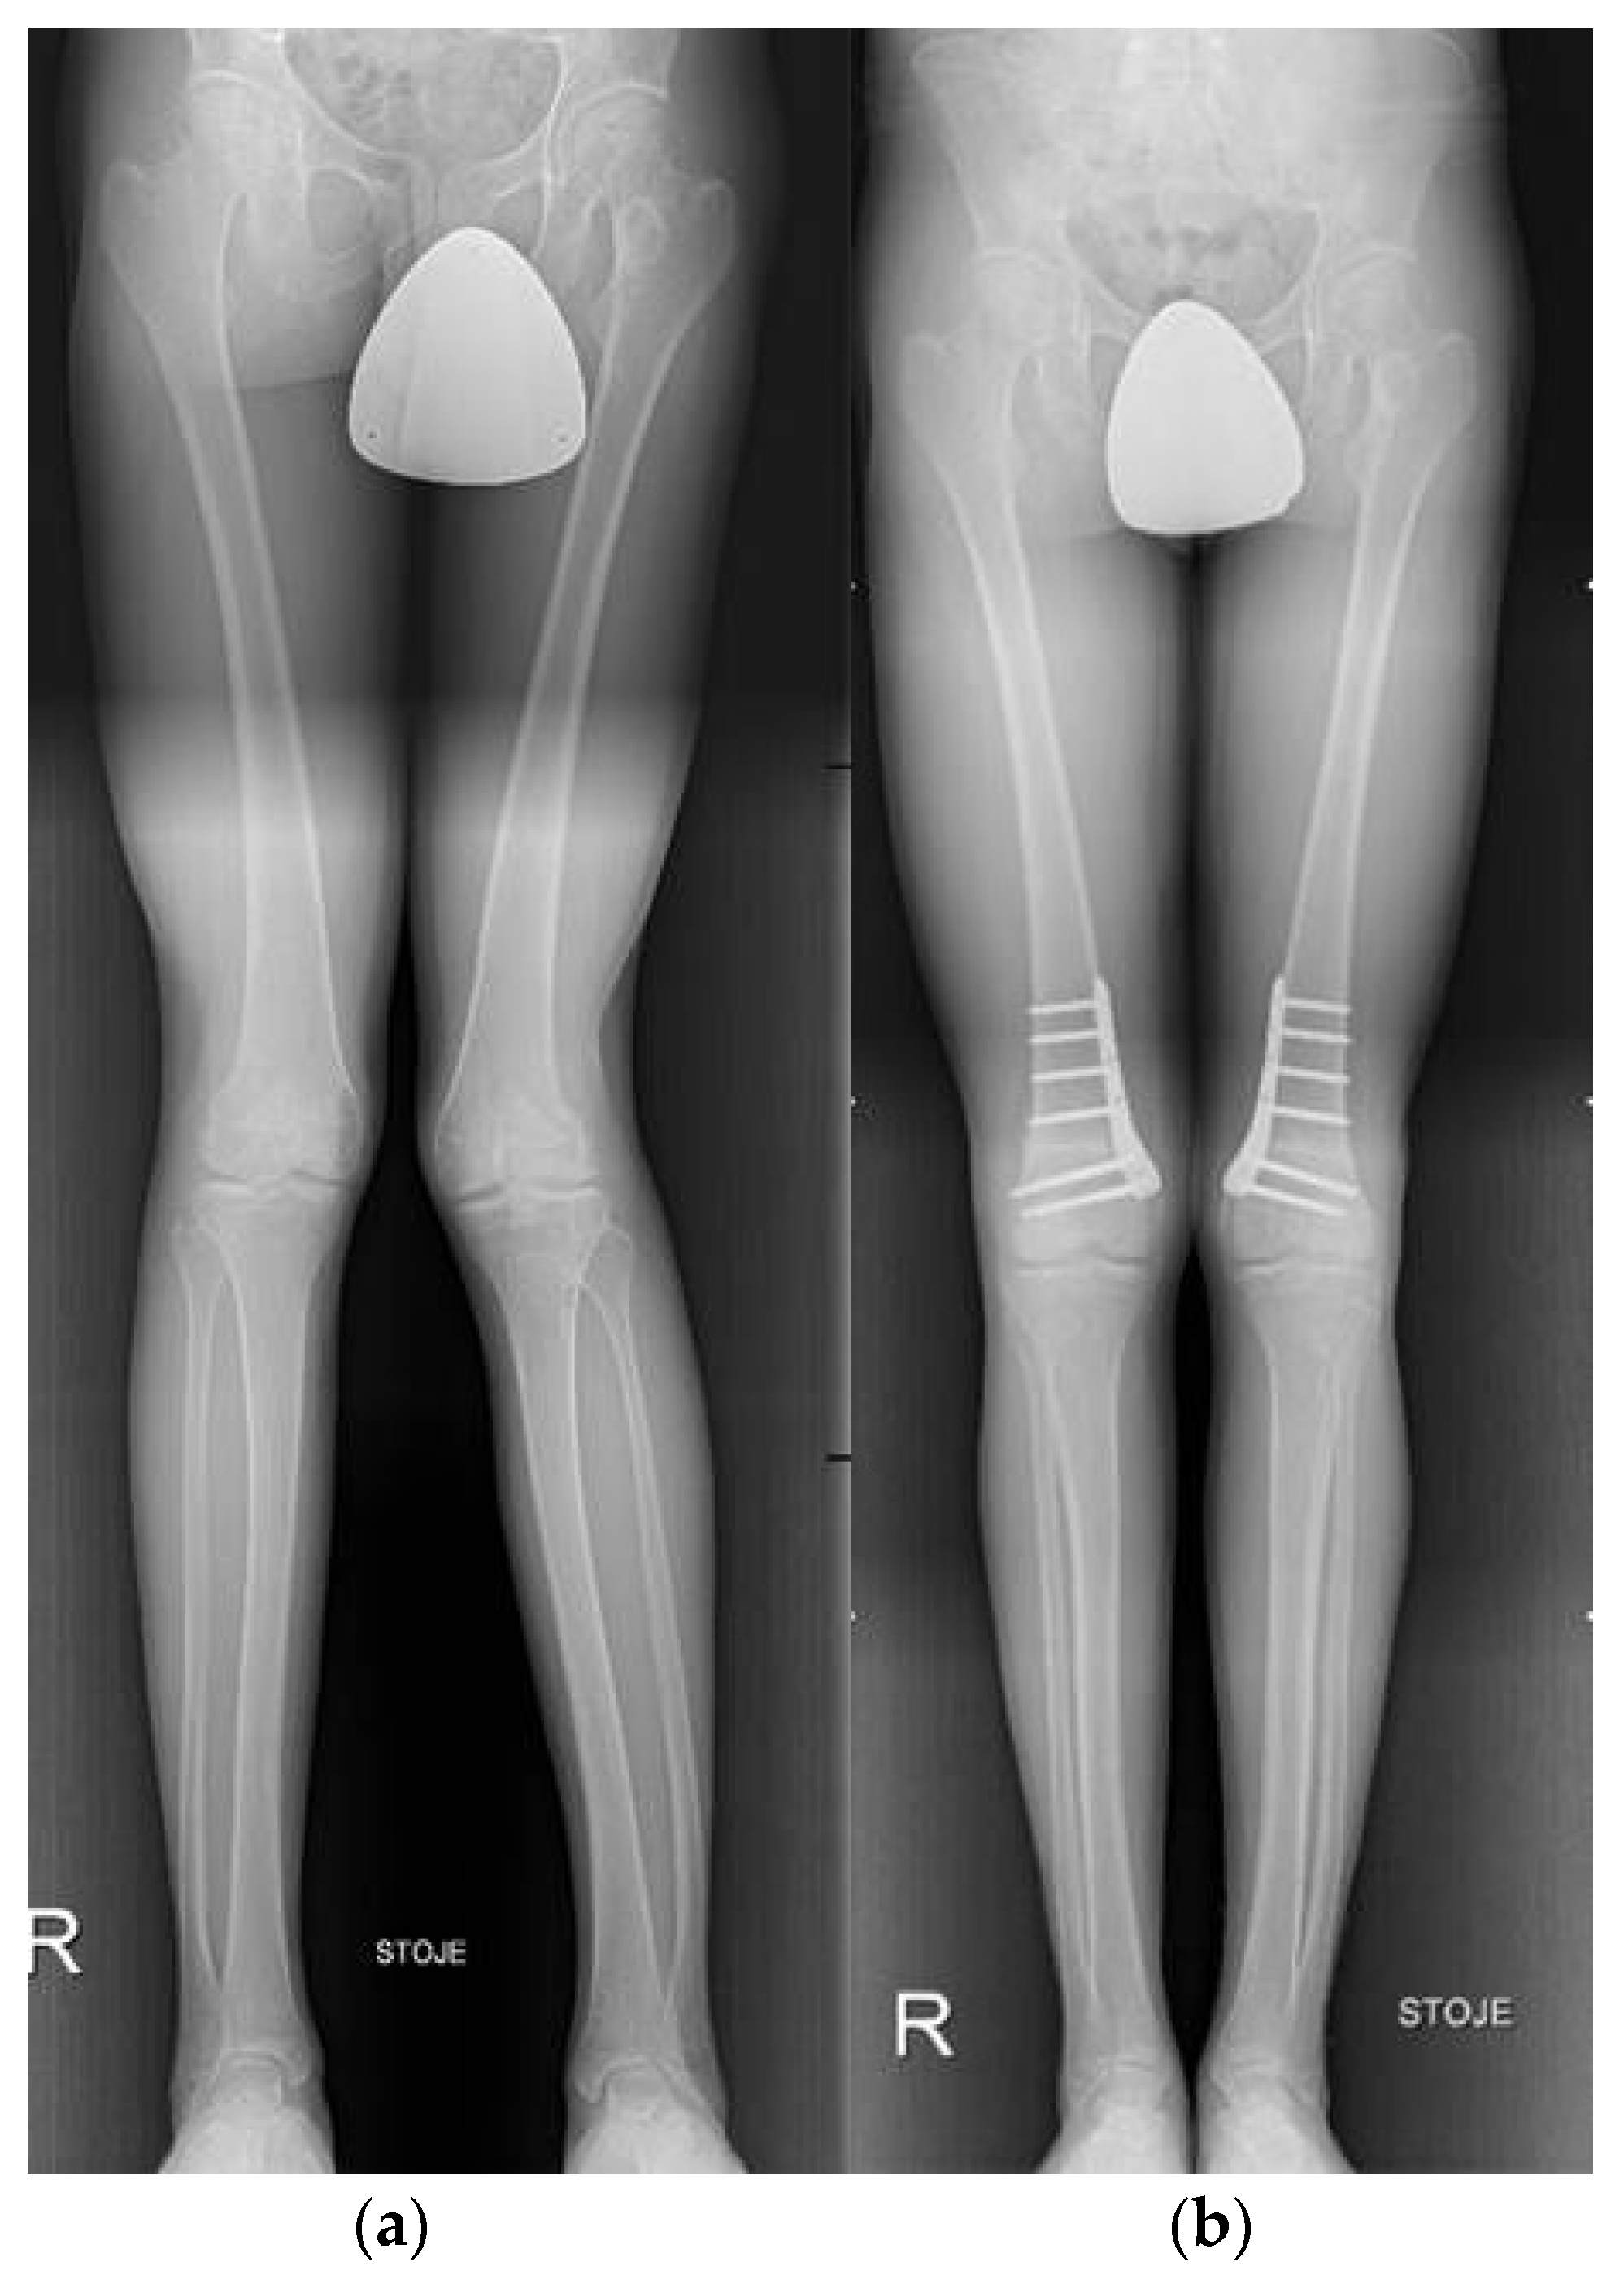

3.6. Knee

- Kanakamedala, A.C.; Hurley, E.T.; Manjunath, A.K.; Jazrawi, L.M.; Alaia, M.J.; Strauss, E.J. High Tibial Osteotomies for the Treatment of Osteoarthritis of the Knee. JBJS Rev. 2022, 10, e21.00127. [Google Scholar] [CrossRef]

- Wolcott, M.; Traub, S.; Efird, C. High Tibial Osteotomies in the Young Active Patient. Int. Orthop. 2010, 34, 161–166. [Google Scholar] [CrossRef] [PubMed]

- Gomoll, A.H. High Tibial Osteotomy for the Treatment of Unicompartmental Knee Osteoarthritis: A Review of the Literature, Indications, and Technique. Phys. Sportsmed. 2011, 39, 45–54. [Google Scholar] [CrossRef] [PubMed]

- Saragaglia, D.; Sigwalt, L.; Rubens-Duval, B.; Chedal-Bornu, B.; Pailhe, R. Concept of Combined Femoral and Tibial Osteotomies. J. Knee Surg. 2017, 30, 756–763. [Google Scholar] [CrossRef]